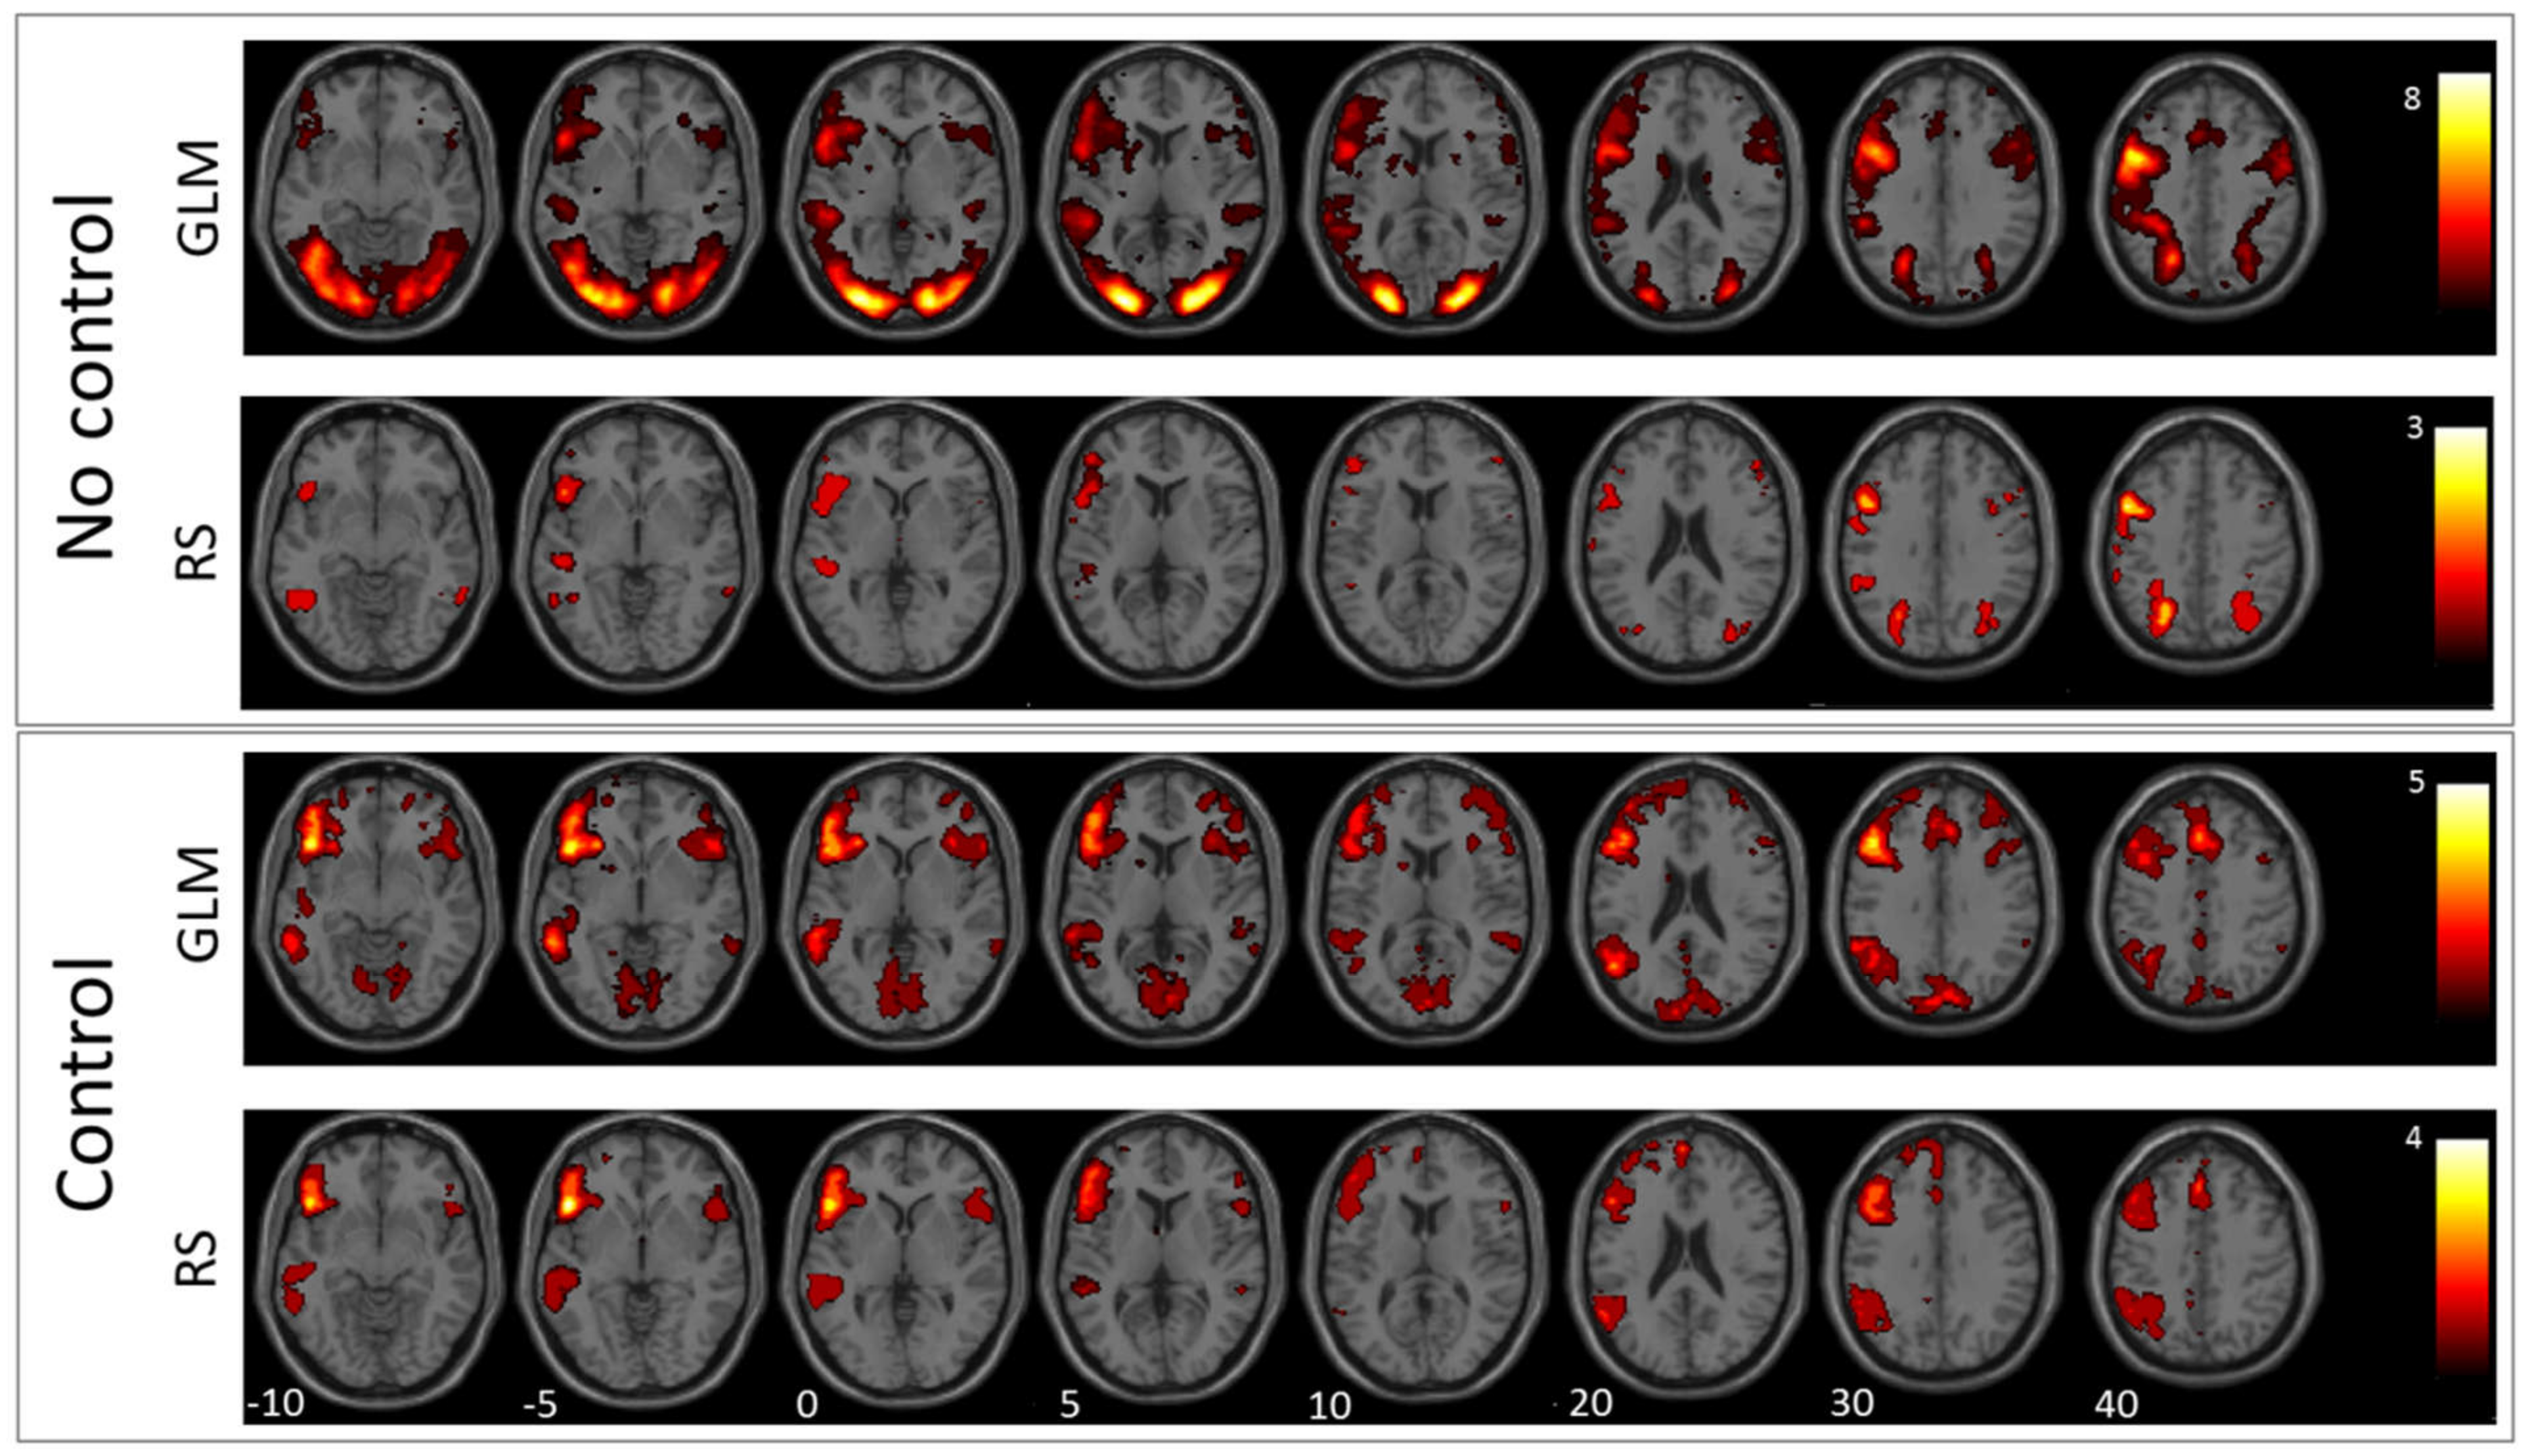

3.1. GLM Results

3.2. RS-fMRI Results